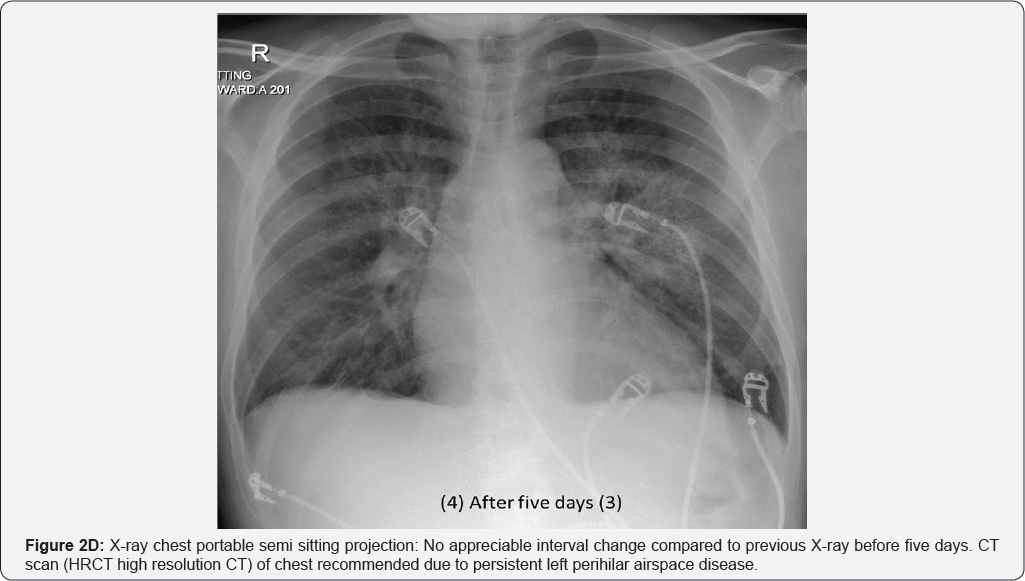

X-Rays and CT during his Hospital stay: (Figure 2A-2E)

Pleural effusion (RT>LT) multiple small mediastinal lymph nodes (arrow in image a & b), likely reactive. Bilateral perihilar airspace diffuse air space opacity and ground-glass attenuation with superimposed interlobular septal thickening and intralobular lines (LT> RT). Common differential of Crazy paving given as well as diagnosis of pulmonary edema (uncommon cause of crazy paving) given in view of history of CHF and improvement by treatment. Superimposed infection is likely in view of high inflammatory markers (Figures 3A & 3B).